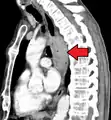

Esophageal cancer as shown by a filling defect during an upper GI series

Although an occlusive tumor may be suspected on a barium swallow or barium meal, the diagnosis is best made with an examination using an endoscope. This involves the passing of a flexible tube with a light and camera down the esophagus and examining the wall, and is called an esophagogastroduodenoscopy. Biopsies taken of suspicious lesions are then examined histologically for signs of malignancy.

Additional testing is needed to assess how much the cancer has spread (see § Staging, below). Computed tomography (CT) of the chest, abdomen and pelvis can evaluate whether the cancer has spread to adjacent tissues or distant organs (especially liver and lymph nodes). The sensitivity of a CT scan is limited by its ability to detect masses (e.g. enlarged lymph nodes or involved organs) generally larger than 1 cm.[43][44] Positron emission tomography is also used to estimate the extent of the disease and is regarded as more precise than CT alone.[45] PET/MR as a novel modality has shown promising results in preoperative staging with fair feasibility and good correlation in comparison to PET/CT. It can enhance tissue differentiation with lowering the radiation dose to the patient.[46] Esophageal endoscopic ultrasound can provide staging information regarding the level of tumor invasion, and possible spread to regional lymph nodes.